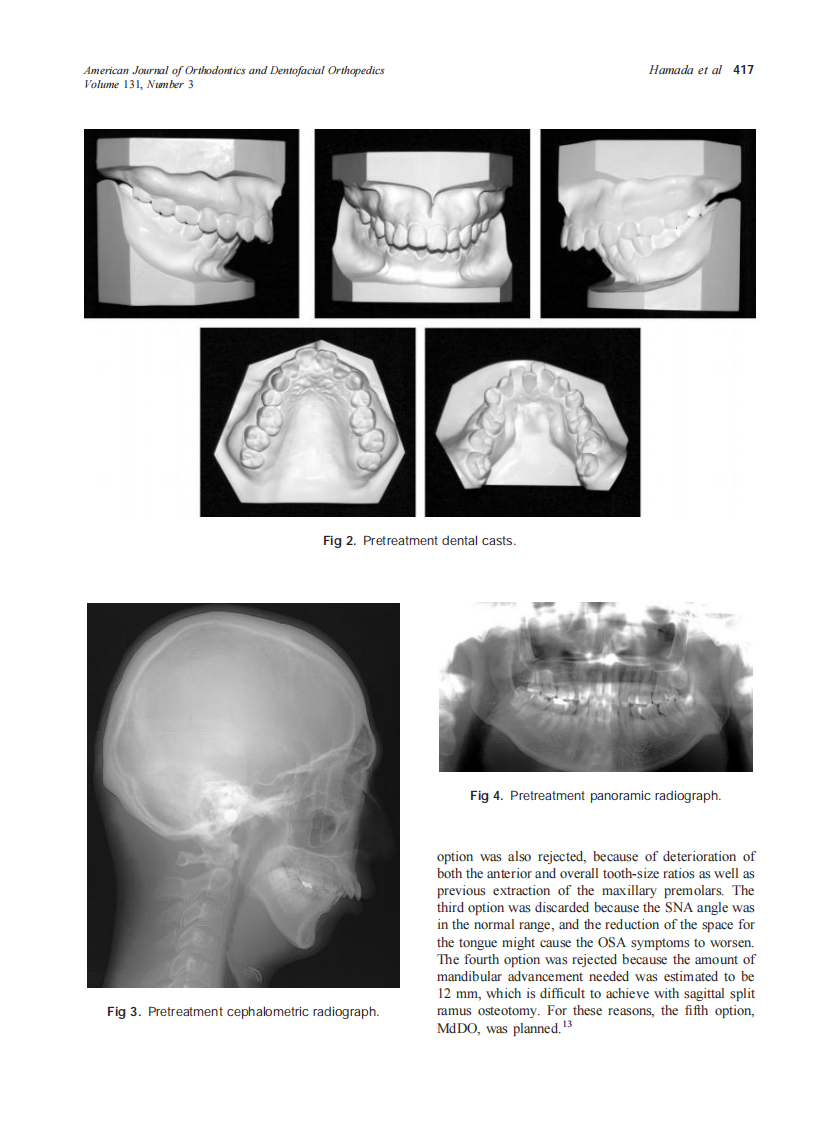

2007_131_3_415_425_Hamada.pdf